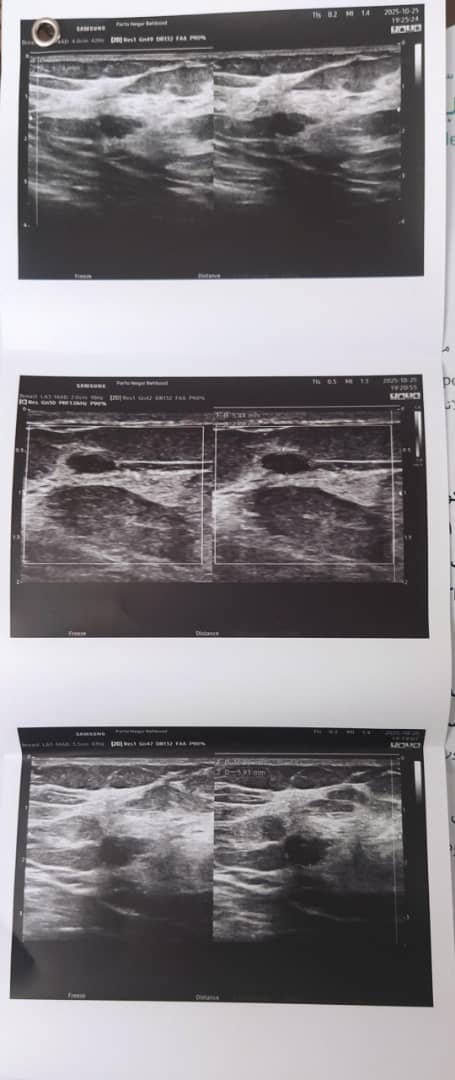

دختر من در سن 13 سالگی به تشخیص و توسط شما برای سینه فیبروآندوم جراحی شد که عمل بسیار خوبی بود ، پس از 11سال در سن 24 سالگی دوباره هر دو سینه اش بافت فیبروآندومی پیدا کرده که مدارک آن برایتان پیوست می شود ، لطفا مرا راهنمایی کنید و در صورت نیاز به پیگیری و درمان ، پزشک معتمدی را معرفی نمایید . سپاس

در این بررسی اخیر که فرستاده اید فیبروآدنوم گزارش نشده است و ضایعه کوچکی که شبیه توده چریب بوده هم بسیار کوچک است و در حال حاضر نیازی به کار بیشتری نیست.

سونوگرافی را پیش کسی انجام بدید که دوره فوق تخصصی سونوگرافی پستان گذرانیده باشد.

بررسی دوره ای هر شش ما زیر نظر یک جراح کافی است.